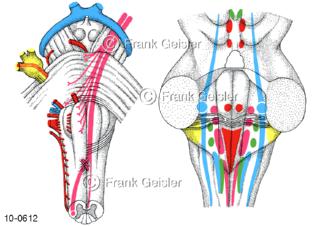

Bildergalerie Nervensystem

Bilder zum Nervensystem,dem Gehirn, Teil des zentralen Nervensystem, Zentralnervensystem ZNSmit Rückenmark, Abbildungen zum Nervengeflecht (Nervenplexus), die Verflechtungen von Nervenfasern, aus der Wirbelsäule hervortretende Nervenäst sowie Nervenzellen der Nerven